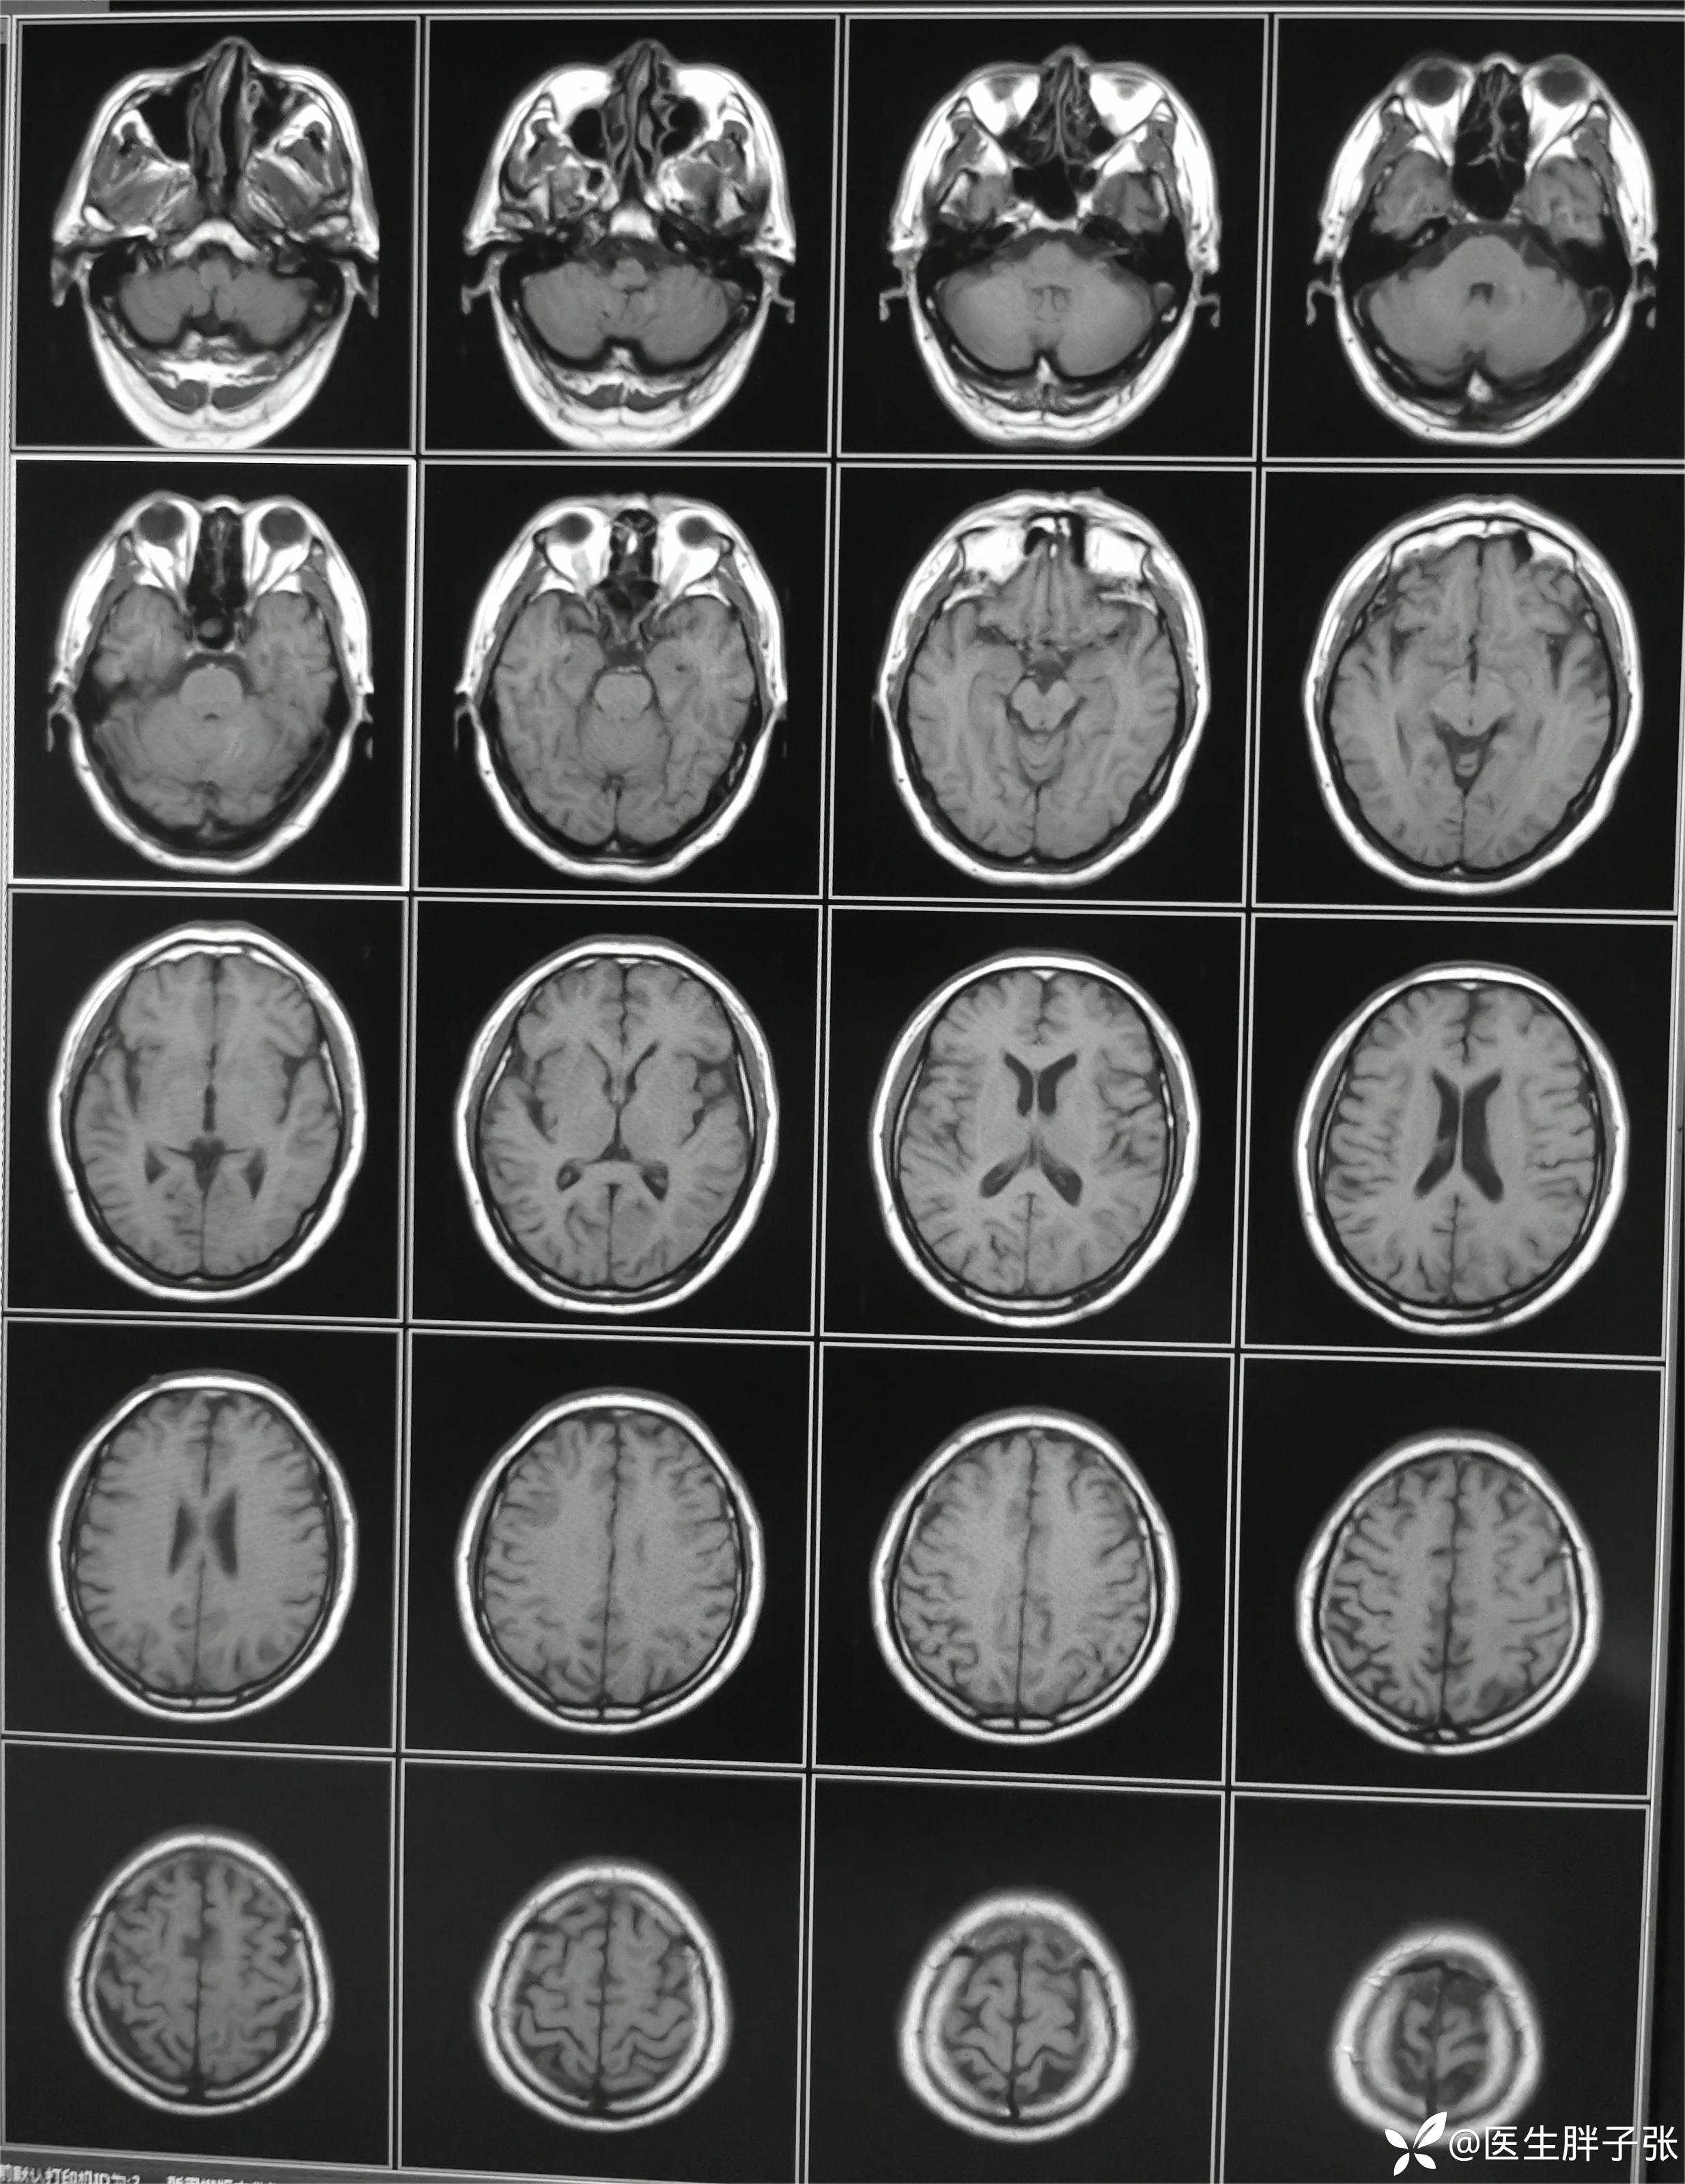

颅脑MR回报左侧顶叶新近梗死灶;多发腔隙性脑梗死及缺血灶;MRA未见异常。

再次查看核磁,考虑患者左侧顶枕叶及右侧枕叶脑组织存在混杂信号。